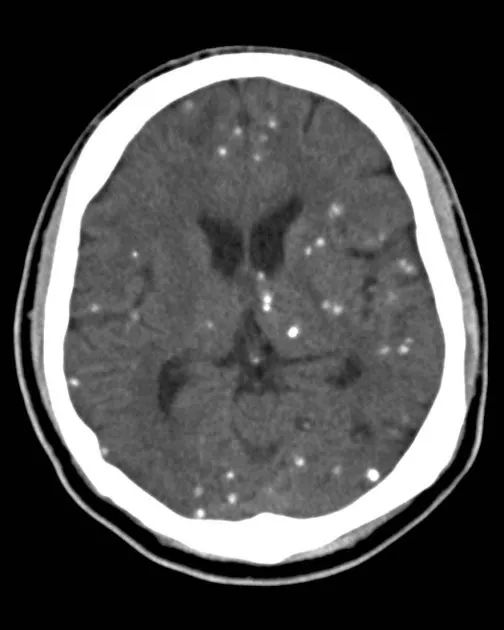

包括甲状旁腺功能减退、假性甲状旁腺功能减退、Fahr病等。这类疾病以前大家都很熟悉,甲状旁腺功能减退意味着甲状旁腺素降低,血钙降低,血磷升高,出现转移性钙化(基底节区常见)。假性甲状旁腺功能减退属于遗传性疾病,患者的甲状旁腺激素受体异常,患者临床表现和生化表现与甲状旁腺功能减退一样,但是其甲状旁腺激素是升高的。患者可伴发育异常和智力障碍,骨营养不良等。假-假性跟假性患者临床表现、影像学表现相同,但是患者生化及甲状旁腺激素全都正常。Fahr’s病多为家族遗传性,发病患者多为40~50岁,临床表现多种多样,包括神经、精神、认知等方面的异常。

1. Fahr’s病

疾病见下图。